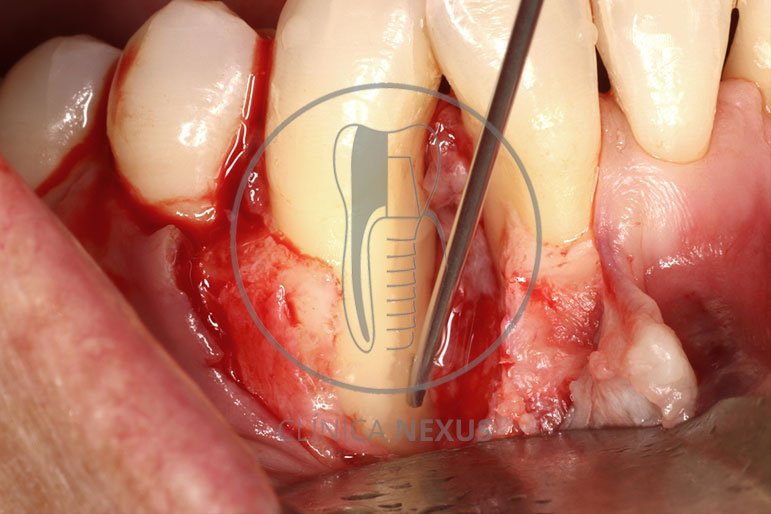

Tratamiento de defectos periodontales infraóseos en sector antero-inferior empleando gel de amelogeninas (Emdogain®) en combinación con un aloinjerto óseo (Biobank®). Paciente de 64 años, sin problemas médicos de relevancia, que presenta una periodontitis leve generalizada, pero asociada a presencia de defectos óseos verticales profundos a nivel de los espacios interdentales entre los caninos y los incisivos laterales inferiores. Tras la pertinente fase higiénica, se llevó a cabo una cirugía periodontal regenerativa, en la que, tras eliminar el cálculo subgingival (factor causal), se empleó una combinación de amelogeninas con un aloinjerto, para promover la regeneración tisular del periodonto perdido. Las imágenes clínicas y radiológicas, al año de seguimiento, reflejan un resultado terapéutico óptimo, con regeneración completa del tejido periodontal y mejora del pronóstico de los dientes involucrados.